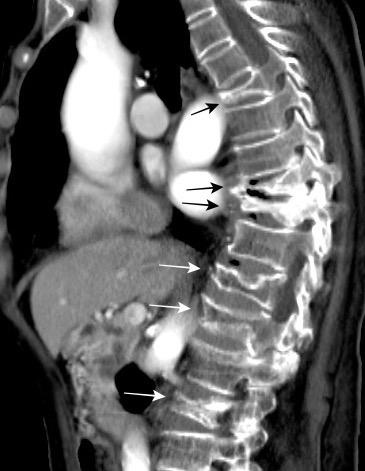

Líneas paraespinales formando un “paréntesis” por encima del diafragma. El signo señala el origen “intratorácico” de la lesión.

Conrad A et al. Pott’s disease associated with large and multiple abscesses in a 30-year-old migrant from Chad. BMJ Case Rep 2018

(lesiones toracoabdominales) La divergencia de las líneas paraespinales apunta a lesión toracoabdominal, que desde el tórax desciende y penetra en el abdomen.

Signo del “iceberg” positivo en Tb vertebral

Afectación por vía hematógena. Región dorsolumbar más frecuente. Afectación inicial: irregularidad de los platillos vertebrales, disminución del disco intervertebral con esclerosis ósea adyacente. Kim. Radiographics.2001